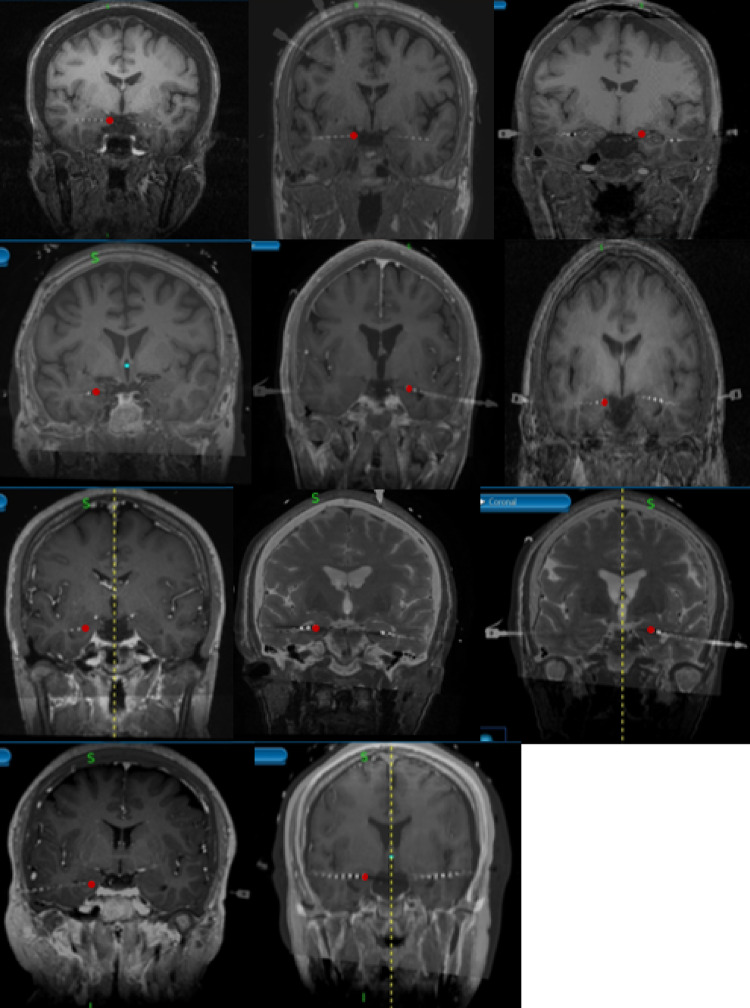

Though the hippocampus is known for its role in memory and navigation, growing evidence has suggested that it is involved in voluntary movement. By investigating whether the hippocampus is active during movement preparation, we can understand its role in motor control. In this study, we utilized a Delayed Reach task to measure beta-band (13-30 Hz) amplitude changes in the human hippocampus during movement preparation. We hypothesized to observe beta-band event-related desynchronization (ERD) during the movement preparation phases. Eleven patients diagnosed with drug-resistant epilepsy were implanted with stereoelectroencephalographic (SEEG) depth electrodes and SEEG signals were recorded. We pre-processed the raw neural signals using the zap-line noise removal technique and re-referenced the data using a novel weighted electrode shaft re-referencing technique. The beta-band Power Spectral Density (PSD) was calculated using multi-taper spectral analysis and trial averaged PSD between task phases was compared using a cluster-based permutation test. We then compared modulation between ipsilateral vs. contralateral contacts using the group-level Yate's z-test. 91% of participants and 46.8% of hippocampal gray matter contacts (n = 149) exhibited significant beta-band ERD during the Delay phase compared to baseline. During the Response phase, 100% of participants and 69.8% of hippocampal gray matter contacts exhibited significant beta-band decreases. We observed no significant difference between ipsilateral and contralateral contacts (p > 0.05). This study is the first to demonstrate hippocampal beta-band modulation during movement preparation, implying that the hippocampus may be involved during the movement processing.

Abstract Image